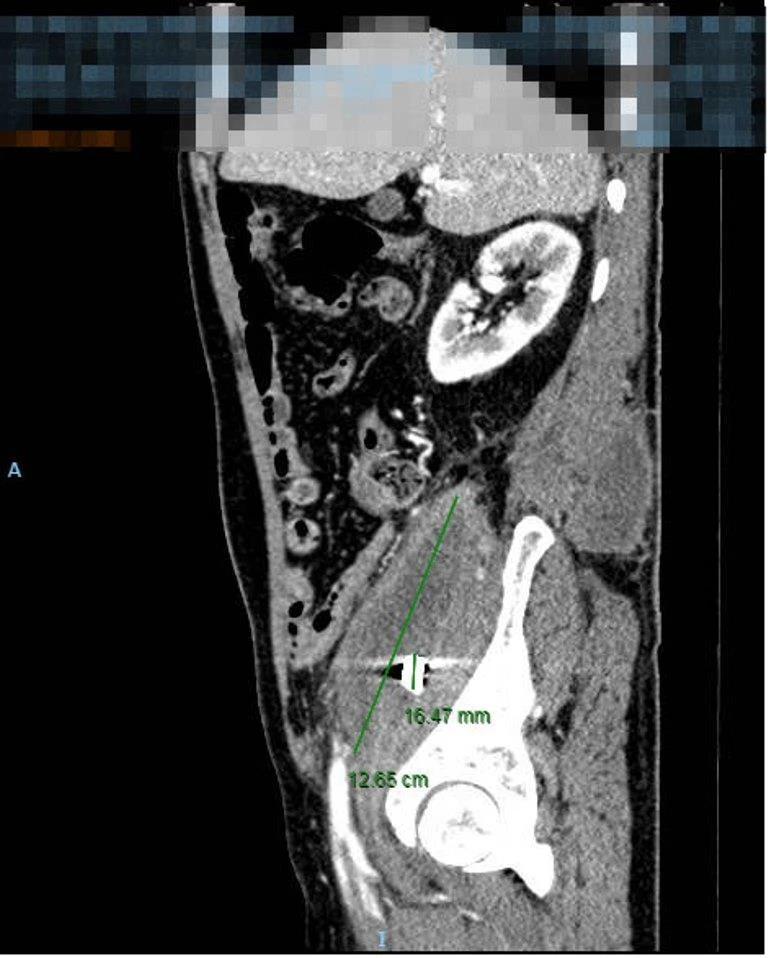

Qua thăm khám toàn diện, chụp cắt lớp điện toán vùng bụng tại BV ĐH Y dược TP.HCM, các BS phát hiện bệnh nhân có một ổ áp xe to tại vùng cơ thắt lưng chậu phải, ổ áp xe đã lan ra sau lưng. Ghi nhận hình ảnh nghi ngờ của mảnh kim loại, tương ứng với mảnh đạn từng kẹt lại trong người ông K.

Kết quả xét nghiệm máu cho thấy tình trạng bạch cầu máu của ông K. tăng cao, dấu hiệu nhiễm trùng nặng. Với chẩn đoán áp xe lớn cơ thắt lưng chậu bên phải nghi do mảnh đạn, các BS khoa Ngoại tiêu hóa của BV đã chỉ định mổ cấp cứu cho ông K.

Ổ áp xe khổng lồ ở thắt lưng người đàn ông. Ảnh: BVCC